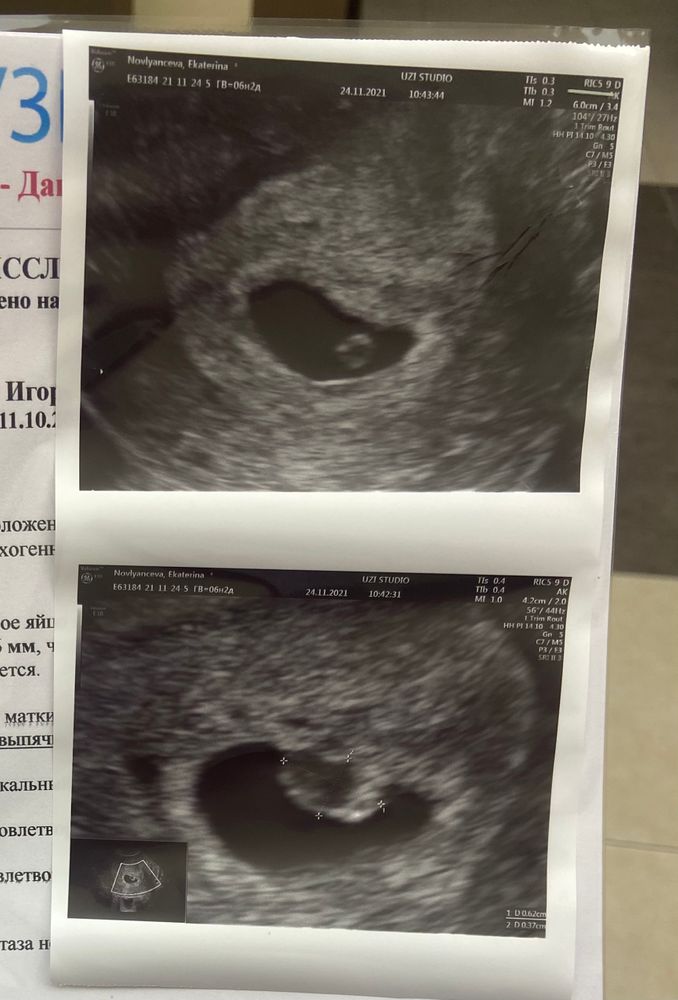

Добрый день. У кого было такое на 6 неделе? На узи увидели что-то. Либо сосудисто нервный пучок либо хориональное выпячивание. Гинеколог сказала возможно такое из-за воспаления в мазке. И мажущие выделения тоже может быть из-за этого. Выписали лекарства и контроль через 2 недели. У кого такое было?

Добрый день! Вижу у вас все отлично, слава богу. Подскажите, как разрешилась ситуация? У меня девятая неделя, киста хориона (выпячивание) 15мм. Стресс жуткий… хотя сказали что такое бывает - может рассосаться, а может остаться и вроде не мешает эмбриону. Буду благодарна за ответ🌹